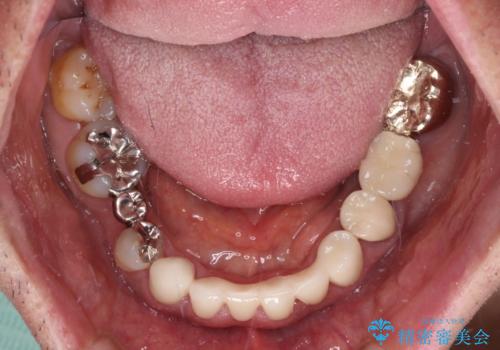

下顎の乳歯は支台歯として機能することは困難と思われたので、事前に抜歯をし、上顎の矯正治療終了のタイミングに合わせて、セラミックブリッジにて補綴治療することとしました。

前歯部はディープバイトという、上顎前歯が下顎前歯に深く覆い被さる咬合であったので、理想的には全顎矯正が必要となりますが、今回は患者希望により前歯部のみの部分矯正で対応しました。そのため下顎犬歯の神経を取り除くことになってしまったのは心残りであります。